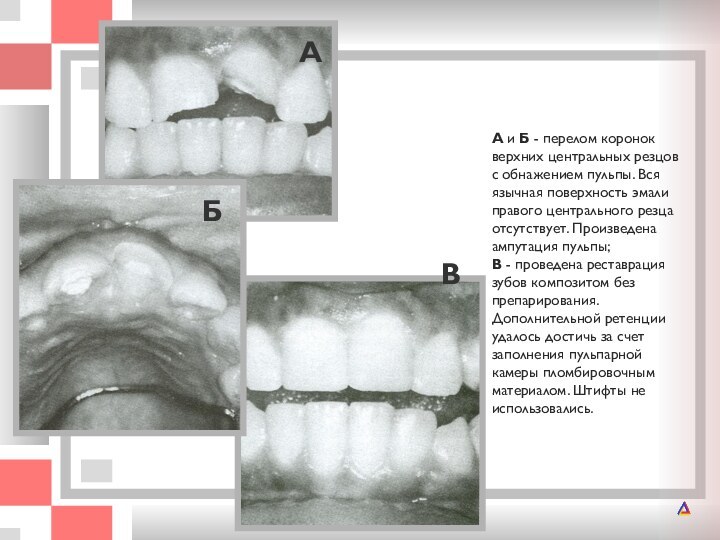

А и Б - перелом коронок верхних центральных резцов с обнажением

резцов с обнажением пульпы. Вся язычная поверхность эмали правого

центрального резца отсутствует. Произведена ампутация пульпы; В - проведена реставрация зубов композитом без препарирования. Дополнительной ретенции удалось достичь за счет заполнения пульпарной камеры пломбировочным материалом. Штифты не использовались.